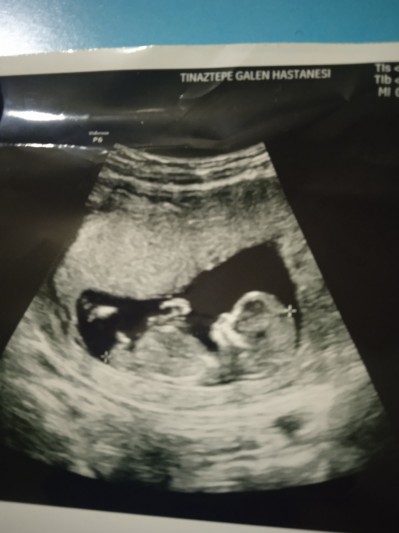

Bugün hastaneye gittim kızlarrr ikili tarama testi de yapıldı ultrasonda ense kalınlığı burun kemiğine bakıldı çok şükür herşey çok güzel bebeğim sağlıklı doktor tahminde bulundu ama kesin gibi de konuştu erkek diyor sizde yorum yaparmisiniz fotoğrafa bakıp

Gebelik haftası 12

Benim oğlumun ultrason görüntüsüne çok benziyor, sanki bi çıkıntı var annesi sağlıkla alın kucağınıza inşallah